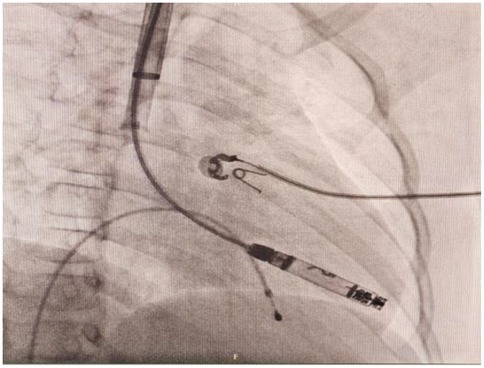

Following successful induction of anesthesia, ultrasound-guided RIJ vein puncture was performed with placement of a 6-Fr sheath. Following venography, a vascular closure device was preplaced (Perclose ProGlide, Abbott). A pigtail catheter was then advanced over a guidewire into the right ventricle via the RIJ vein. Angiography was performed in RAO 30°/0° and LAO 45°/0° projections to delineate the right ventricular anatomy and identify optimal apical/septal pacing sites. The pigtail catheter was then exchanged for an Amplatz Super Stiff guidewire (0.035 cm, 260 cm), allowing sequential venous dilation from 8-Fr to 24-Fr. The 27-Fr Aveir introducer sheath (outer diameter) was advanced to the SVC- right atrial junction after thorough flushing. The tapered dilator was then carefully removed, and the sheath was connected to heparinized saline infusion. Subsequently the Aveir delivery catheter (25-Fr) was introduced through the 27-Fr outer sheath. Under fluoroscopy, the delivery system was navigated across the tricuspid valve to an apical-RV septal position. Angiography confirmed optimal device placement and septal position (Figure 3), with mapping demonstrating an R-wave amplitude of 4.0 milliVolts (mV), impedance of 330Ω, pacing threshold of 1.75V@0.4 milliseconds (ms), injury current of 1.5 mV. The Aveir leadless pacemaker was deployed in the RV apical septum with 1.4 clockwise rotations under fluoroscopic observation. Subsequent deflection testing confirmed stable fixation. Post-deployment electrical measurements showed improved pacing performance with pacing threshold of 0.5V@0.4 ms, R-wave amplitude of 3.8 mV, impedance of 490Ω. The leadless pacemaker was released after final programming to VVI mode at 55 beats per minute (bpm). Catheters were withdrawn under fluoroscopic guidance, and hemostasis was achieved using the pre-deployed PerClose vascular closure device combined with subcutaneous suturing. The patient maintained hemodynamic stability throughout the procedure without complications. Intraoperative programming data for the leadless pacemaker are detailed in Table 1. At one-day follow-up, the device demonstrated a pacing threshold of 0.75V@0.2 ms, impedance of 510Ω, R-wave amplitude of 6.7 mV and predicted longevity of 15.4 years (with 100% pacing). Transthoracic echocardiography confirmed apical-septal position without tricuspid regurgitation or pericardial effusion. At one-month follow up, the catheter insertion site was well-healed, with a pacing threshold of 1.0V@0.2 ms, impedance of 610Ω. The device's predicted longevity was 14.3 years. During follow-up, the child exhibited complete resolution of syncope and resumed age-appropriate activities. This clinical outcome provided substantial reassurance to the patient and parents regarding long-term management.

Figure 3. Right anterior oblique (RAO) projection confirmed the Aveir VR leadless pacemaker was advanced to the right ventricle through right internal jugular vein.